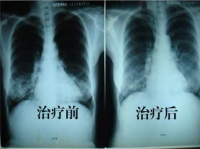

治疗对比图